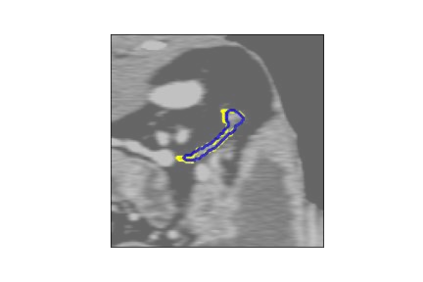

The human annotations are imperfect, especially when produced by junior practitioners. Multi-expert consensus is usually regarded as golden standard, while this annotation protocol is too expensive to implement in many real-world projects. In this study, we propose a method to refine human annotation, named Neural Annotation Refinement (NeAR). It is based on a learnable implicit function, which decodes a latent vector into represented shape. By integrating the appearance as an input of implicit functions, the appearance-aware NeAR fixes the annotation artefacts. Our method is demonstrated on the application of adrenal gland analysis. We first show that the NeAR can repair distorted golden standards on a public adrenal gland segmentation dataset. Besides, we develop a new Adrenal gLand ANalysis (ALAN) dataset with the proposed NeAR, where each case consists of a 3D shape of adrenal gland and its diagnosis label (normal vs. abnormal) assigned by experts. We show that models trained on the shapes repaired by the NeAR can diagnose adrenal glands better than the original ones. The ALAN dataset will be open-source, with 1,594 shapes for adrenal gland diagnosis, which serves as a new benchmark for medical shape analysis. Code and dataset are available at https://github.com/M3DV/NeAR.